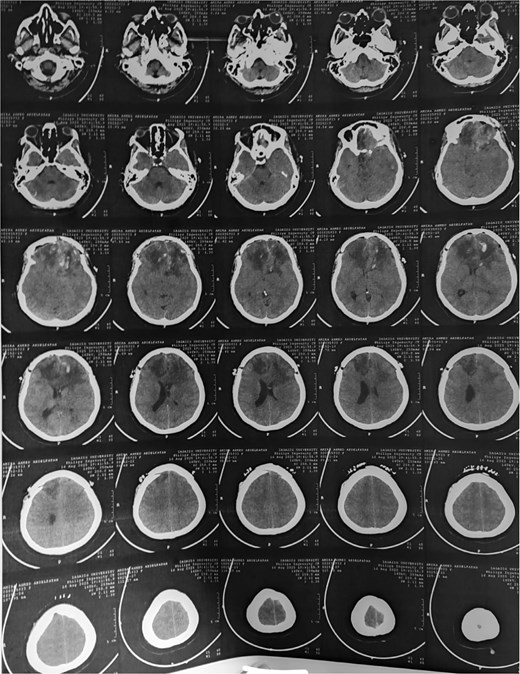

A 44-year-old right-handed woman presented with a two-month history of headache and blurred vision. Her medical history included hypertension and type 1 diabetes mellitus. She reported gradually worsening intermittent headache and bilateral visual blurring, more pronounced in the right eye. Symptoms exacerbated with physical exertion and were unrelieved by analgesics, leading to her referral. Examination revealed a conscious, alert patient with right eye proptosis. Visual acuity was 6/6 (left eye) and 6/9 (right eye). Fundoscopy identified bilateral Grade 3 papilledema. Non-contrast brain CT demonstrated a well-defined, isodense, dural-based extra-axial lesion in the left frontal region with a cystic component, measuring approximately 5.5 × 4.3 × 4.2 cm. It was associated with mild perilesional edema, mass effect, and a subtle contralateral falx shift. The initial impression was an atypical meningioma (Fig. 1). Subsequent MRI confirmed a large, falcine-based lesion that appeared isointense on T1- (Fig. 2) and T2-weighted images, demonstrating intense homogeneous enhancement post-contrast (Fig. 3). Signal voids suggested calcifications. The patient underwent gross total excision via a bilateral frontal craniotomy. The tumor was intradural and extra-axial, elevating the frontal lobe and was easily accessible; therefore, neither neuronavigation nor other intra-operative localization aids were utilized. Intraoperatively, the olfactory tract could not be clearly identified. A gap in the anterior cranial base was noted, but as there was no evidence of dural invasion or cerebrospinal fluid leak, no sealant was required. Gross examination of the resected specimen revealed a well-circumscribed, white nodule. Microscopically, sections showed benign spindle cell proliferation with alternating Antoni A and Antoni B areas (Fig. 4). Antoni A regions displayed nuclear palisading and Verocay bodies (Fig. 5), while Antoni B areas were edematous and myxoid (Fig. 6). No mitotic figures or atypia were seen. The definitive diagnosis was a benign olfactory groove schwannoma, notable given the initial radiological suspicion of meningioma. Her postoperative course was uneventful. A postoperative non-contrast CT brain obtained 48 hours after surgery confirmed gross total resection (Fig. 7). She was discharged with scheduled follow-up to monitor recovery and visual symptoms.

Post-op CT brain showing total excision of the tumor leaving mild post-op oedema at tumor bed.